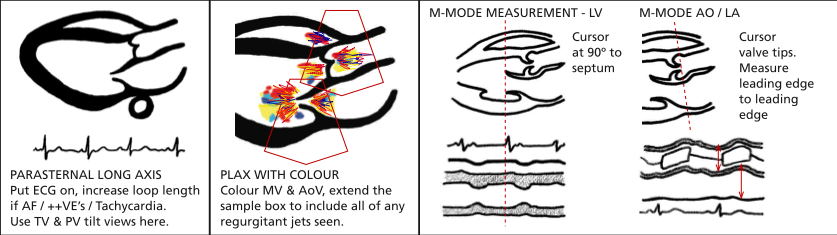

PLAX (Parasternal Long Axis)

Image from BSE website

2nd to 5th intercostal space just next to sternum. Probe marker pointed towards patient’s R shoulder. The higher the level the more likely the LV will be at 90 for M-mode measurements.

2D

Capture a deep clip looking for pleural and pericardial effusions.

Then:

Narrow sector width and reduce depth to focus on area of interest.

Capture a shallower clip with the heart filling the screen. You are not meant to see the apex of the LV.

RVOT uppermost

Aortic valve - right coronary cusp above; non below

Mitral valve - A2 (upper) and P2 (lower) segments visible

Descending aorta behind posterior MV annulus.

M-mode

Through tips of aortic valve leaflets

- Assess valve opening

- Measure aorta (end diastole) and LA (end systole)

Through tips of mitral valve leaflets

- E point (valve tip at most anterior position in early diastole)

- Measure distance from E point to IVS (EPSS)

- A point where valve opens up again in late diastole with atrial systole

Just beyond tips of MV leaflets at 90 degrees to long axis of LV

- Measure septum, LV cavity, posterior wall in systole and diastole

- These can be measured from 2D if the ventricle is not at 90 to your scan line (which is frequently the case)

Colour (Nyquist limit 50-60 cm/s)

Aortic and mitral valves for stenosis and regurg. Do one at a time. The resolution is better the narrower and shallower you have the colour box (cutting off the near field makes no difference).

Measure vena contracta if present (narrowest width of regurg colour).

Colour M-mode for AR if present - measure jet width and calculate as percentage of LVOT width.

LVOT for flow acceleration if septal hypertrophy